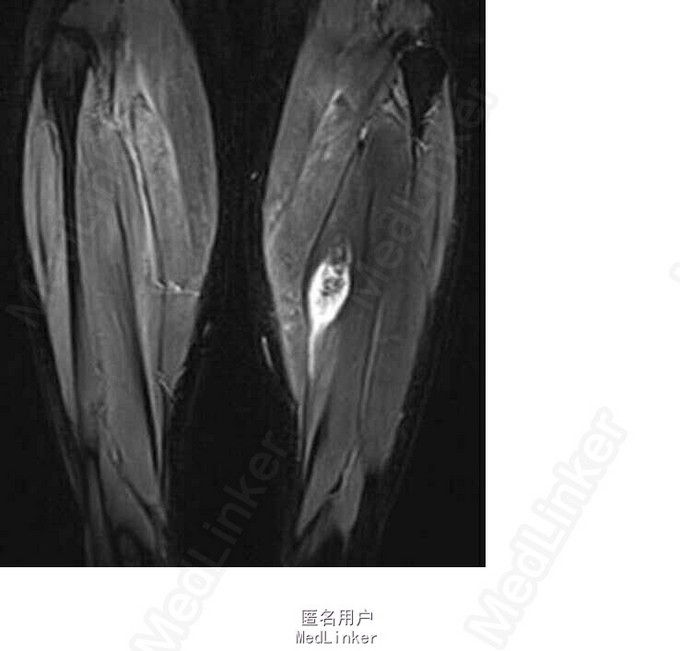

双下肢皮肤未见明显红肿及皮疹;左胫骨中段内侧皮下可及一质硬肿物,大小约5×4cm,无突起皮肤表面,边界清晰,固定,轻压痛。 我院 MRI:左胫骨中段内后侧混杂信号占位,考虑良性病变,血管瘤可能。